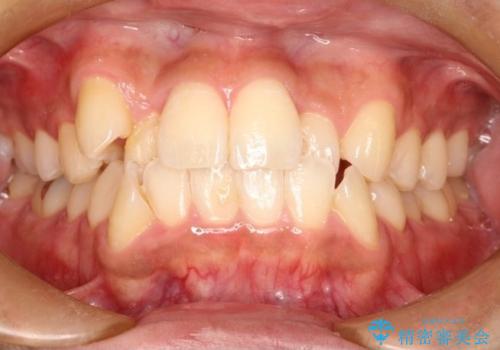

飛び出た八重歯!コンプレックスを払拭!

- 飛び出た八重歯の改善を希望され来院された患者様です。

初診時の歯並びの状態としては、右上の犬歯がいわゆる八重歯の状態であり、強いガタガタが上下ともにある状態でした。

スペースの不足量が多く、抜歯を伴うワイヤー矯正にて治療を行いました。

若干の口元の突出感もあったため、抜歯によるスペースを利用し、がたつきの改善と前歯の後退をを行いました。